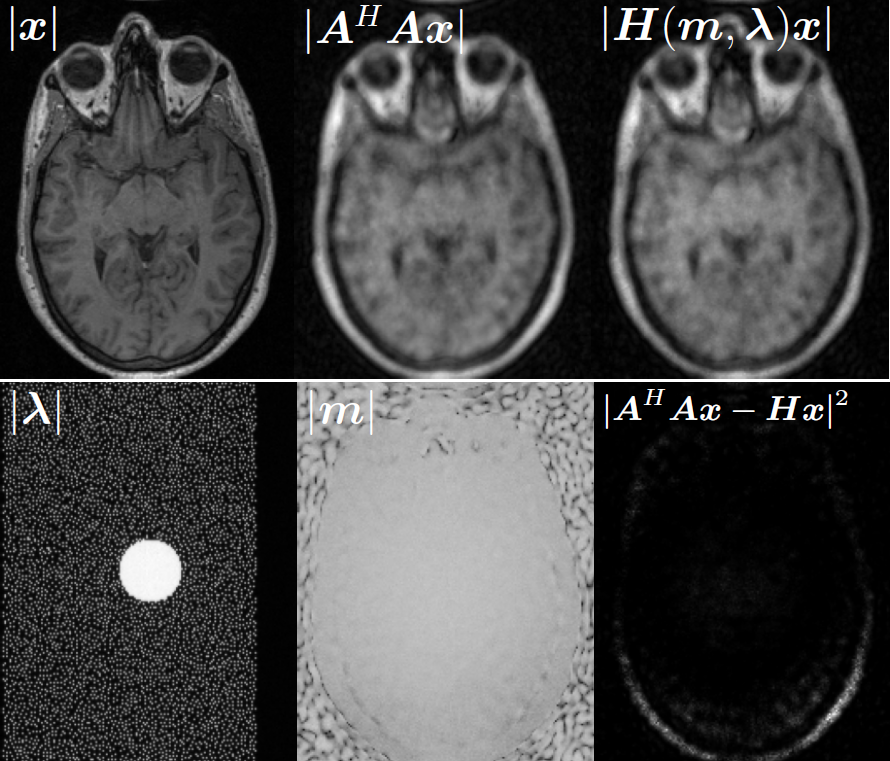

Illustrations of the normal operator approximation on the Walnut-CBCT dataset. (top row) Original volume slice $\vx$, exact normal operator evaluation $\mA^\top \mA \vx$, and approximated normal operator $\mH\vx$. (bottom row) Learned filter $\bm{\lambda}$, learned mask $\vm$, and squared approximation error $(\mA^\top \mA \vx - \mH \vx)^2$.